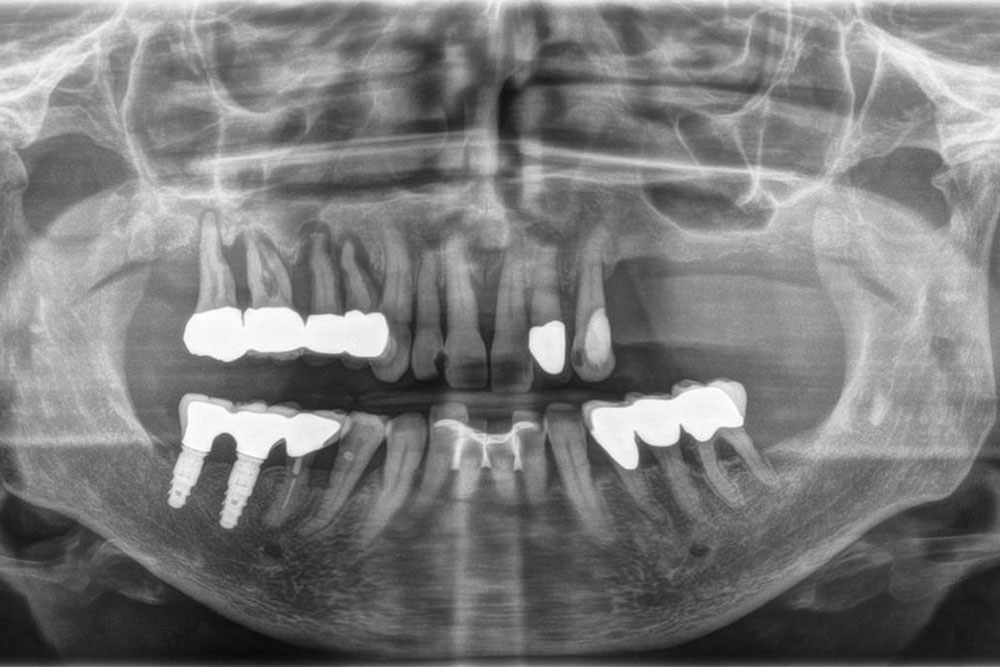

La CT cone beam è diventata sempre più importante per fare diagnosi (il più precise possibile)e nell’Implantologia per la pianificazione del trattamento… in particolare è indispensabile nelle tecniche di Implantologia Computer Assistita. Questa tecnologia viene sempre più impiegata anche in altri campi dell’odontoiatria, come ad esempio l’Endodonzia e l’Ortodonzia.

Durante una scansione Cone Beam, lo scanner ruota attorno alla testa del paziente, ottenendo fino a quasi 600 immagini distinte. Il software raccoglie i dati e ricostruisce le immagini producendo un volume digitale,composto da voxel di dimensione isotropica, dei dati anatomici acquisiti. Quest’ultimi poi vengono “ricostruiti” con software 3D dedicati.